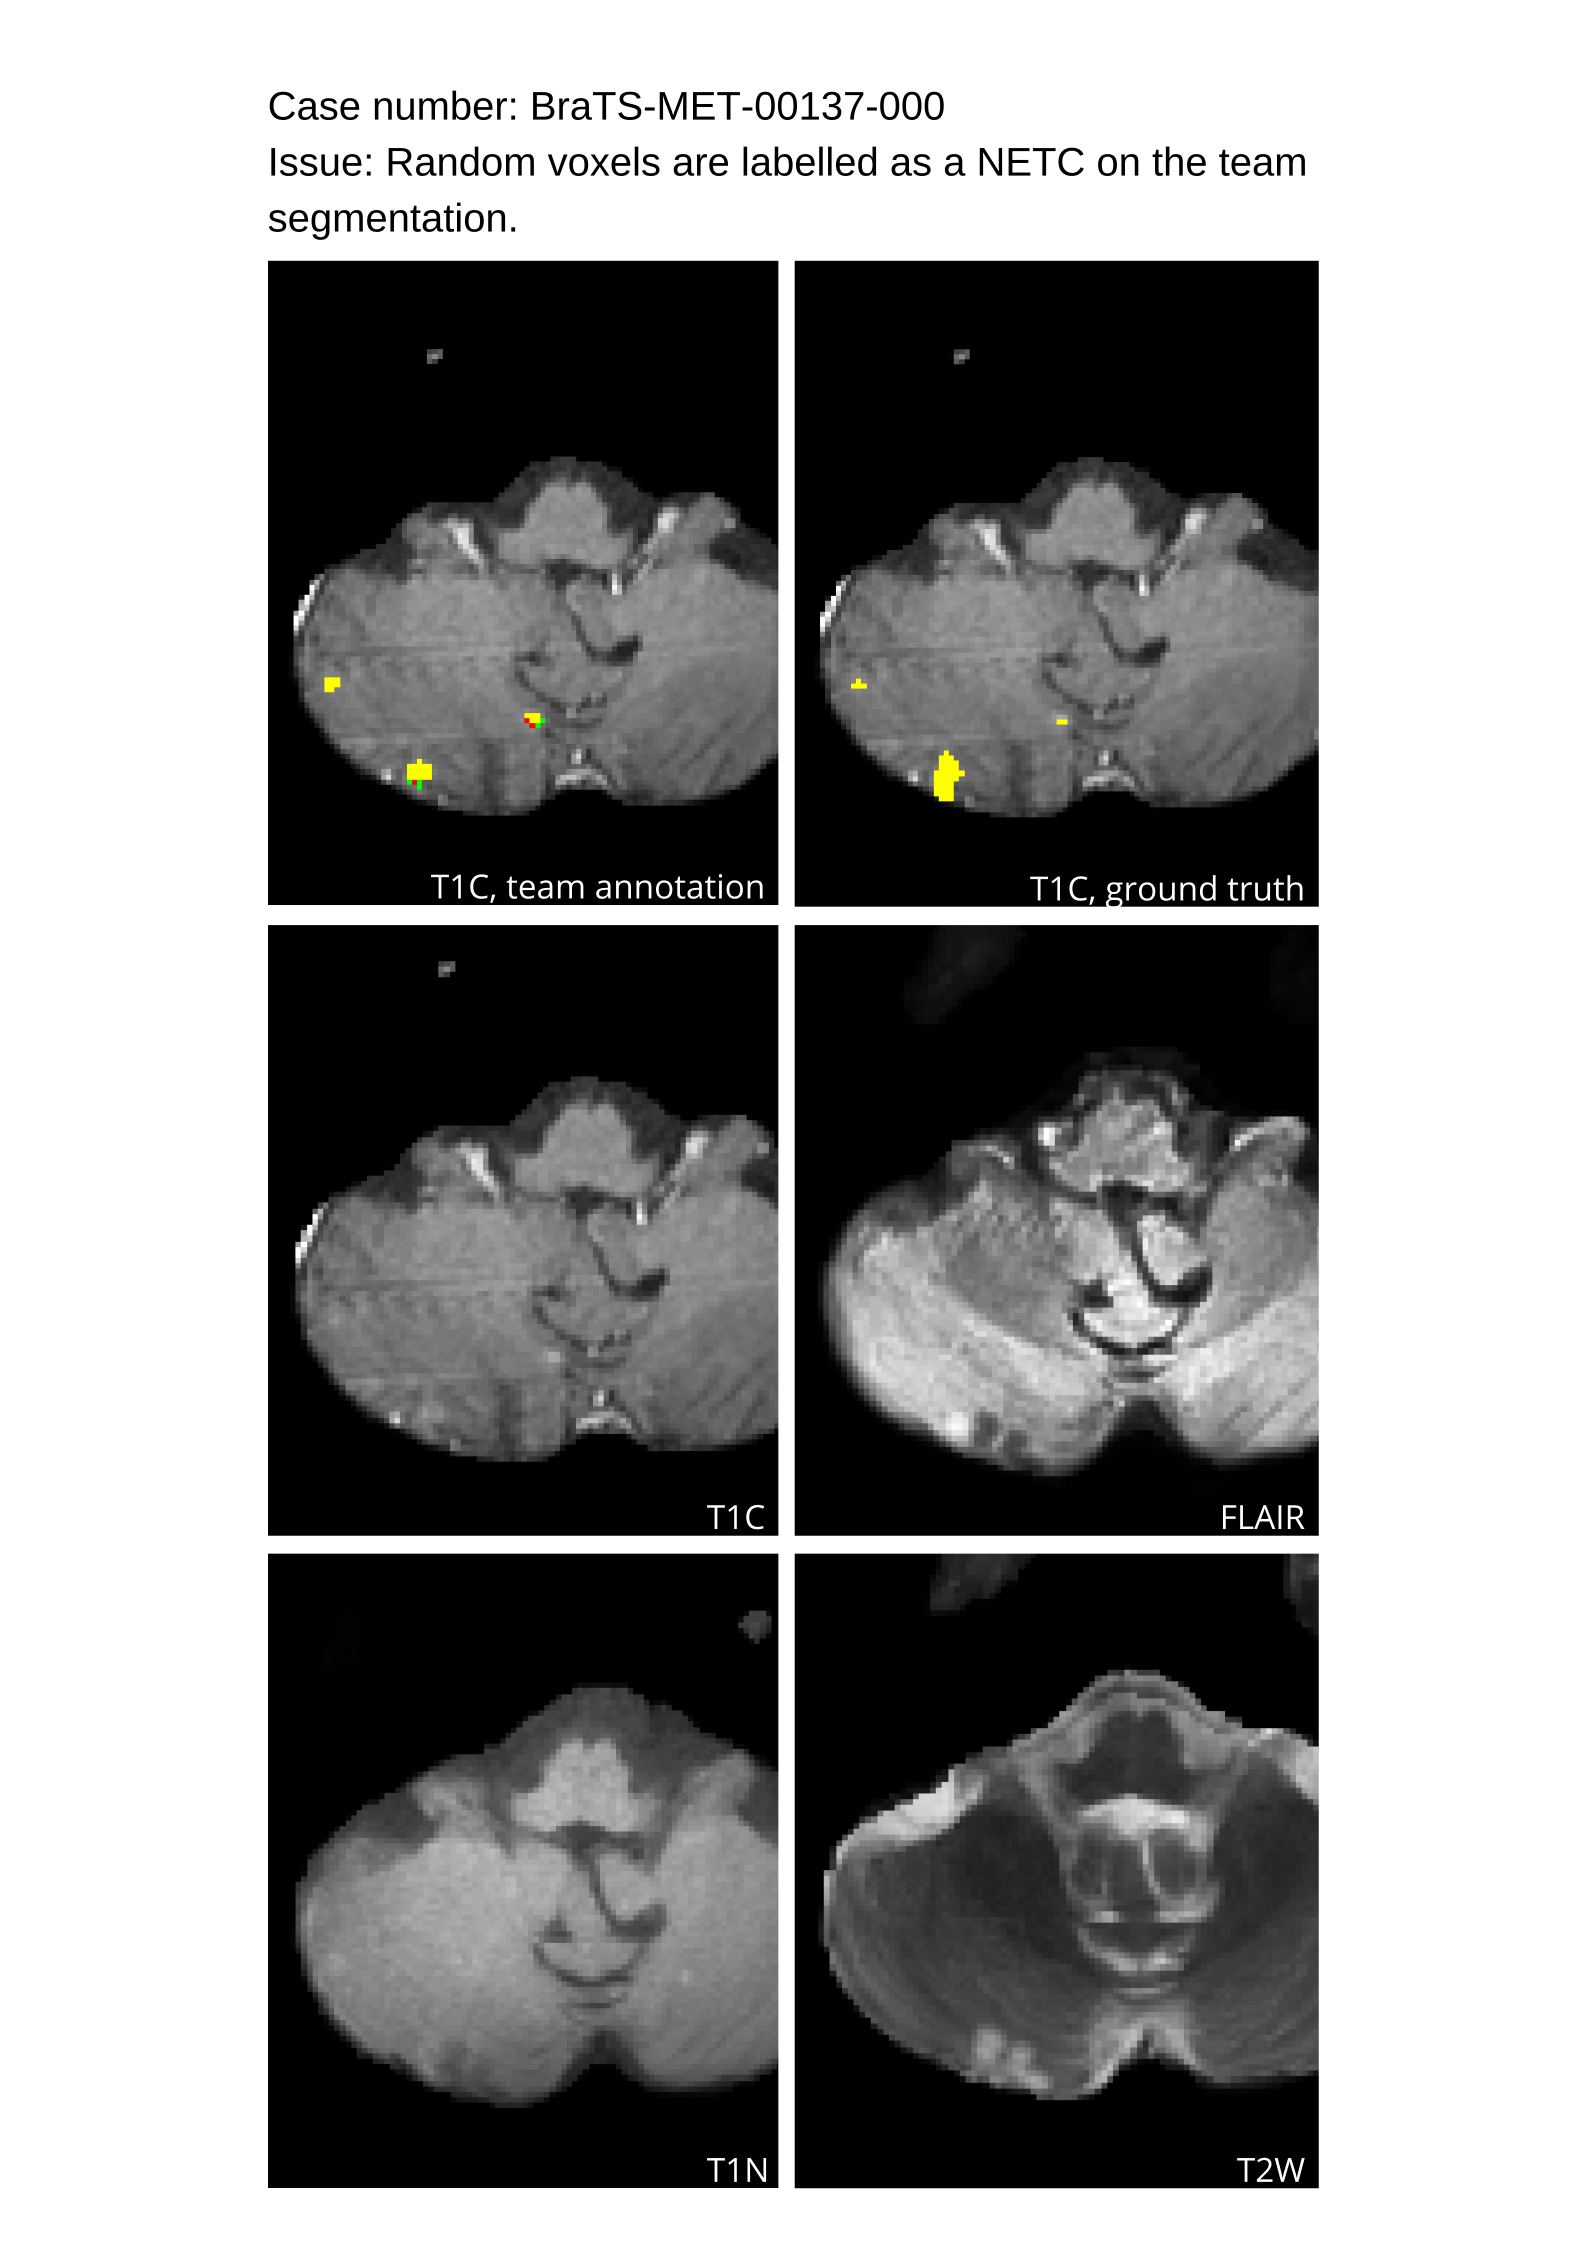

4.9 Common Errors of Automated Segmentations

Based on observations from previous BraTS challenges, common errors in automated segmentations were identified. The most typical errors in the current challenge included:

1. 1.

Automated algorithms missing small metastases. Enhancing metastasis was fused using the minority voting algorithm to aggregate all enhancing tumor voxels identified by the three algorithms. However, many small metastases were missed and were manually segmented by neuroradiology attendings.

2. 2.

Segmentation of white matter changes from microvascular disease. Peritumoral edema segmentations were checked by neuroradiology attendings and modified.

3. 3.

The segmentation of non-enhancing lesions that have intrinsic T1 hyperintensity. Voxels with intrinsic T1 hyperintensity were manually removed from ET segmentations.

These insights led to specific adjustments in the annotation process to enhance accuracy.